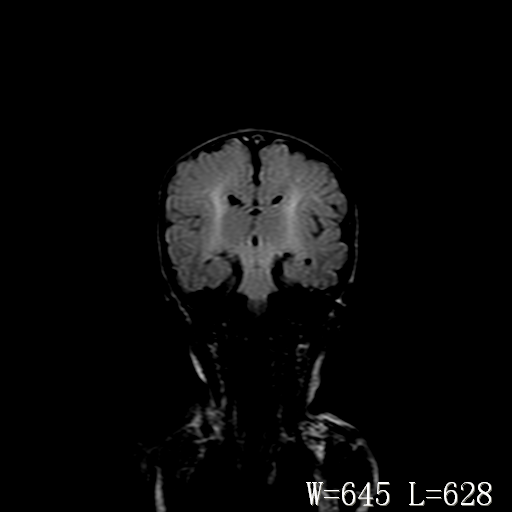

男,4天,发复抽搐1天。

新生儿正常颅脑

hie?

脑干形态欠规则,信号增高,不知怎么解释?

脑干背侧面t1高信号是,新生儿正常已经髓鞘化好的部位